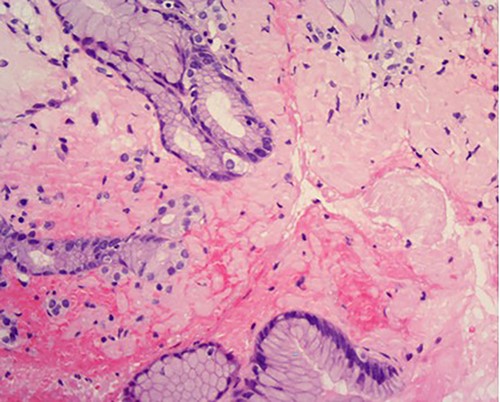

High power of proximal jejunum biopsy showing extensive submucosal deposition of pink amorphous material (H&E ×20).

Amyloid stain on proximal jejunum biopsy as seen under polarized light showing apple-green birefringence (Congo Red ×20).